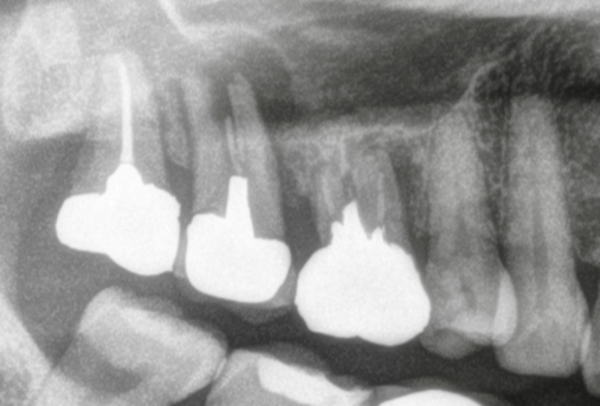

診察したところ、右上の奥から2番目の歯が揺れており、レントゲンではそちらの歯が真っ二つに割れており、大きな感染巣が形成されていました。また奥から3番目の歯には根尖病巣が認められました。

写真は根管治療終了時のものです。抜歯部位は骨がかなり薄く、このままではインプラント治療が困難な状態でした。